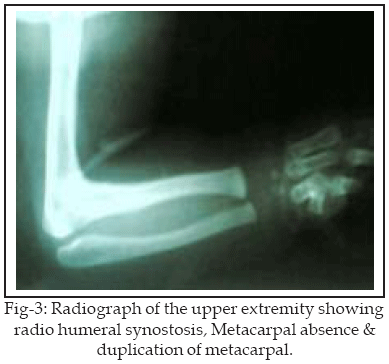

Examination of limbs revealed fixed 90 deg flexion contracture of the right elbow and absence of the thumb. Radiographs confirmed right radio humeral synostosis and skeletal abnormality of right hand including absence of 1st metacarp with hypoplasia and fusion of the 4 th-5th metacarp. (Fig-2,3).

Skull X-Ray and computed tomographic scans confirmed synostosis of both coronal sutures. Sonography of abdominal pelvic and echocardiography was unremarkable. Following a routine pediatrician and preanaesthetic evaluation, she was brought to the operating room. Under general anesthesia with lateral approach, resection of radio humeral synostosis and interposition of local soft tissue was performed. Full range of motion of elbow was achieved (Fig-3,4). A posterior splint was applied and physiotherapy was initiated. The range of elbow and forearm motion was normal in follow up visit at 18 months after surgery.